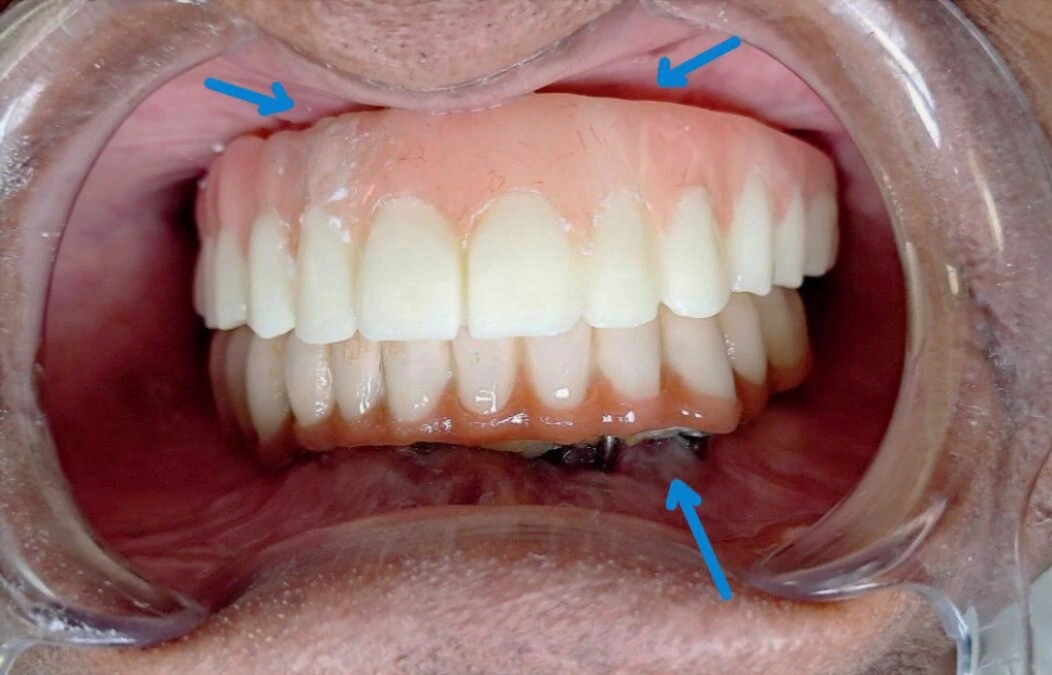

A famous Delhi doctor went for basal implants hoping for “teeth in a week.” Six months later — infection, pain, and massive bone loss. The implants couldn’t even be removed easily; they weren’t FDA approved or retrievable. When no clinic in Delhi NCR took the case, Dr Jyoti Singh at the Center for Dental Implants & Esthetics, Gurgaon rebuilt his jaw with 3D-guided All-on-4 implants. One surgery. Full recovery. Real science, not shortcuts. .

Failed basal implants after 6 months—severe infection, single piece implant resulted in bite misalignment space for food to go under dentures infection, bone loss implant visible

USFDA-approved All-on-4 implants placed with 3D planning & surgical guides, and proper osseointegration protocol

Two Piece implant gives flexibility independent of implant position to place final teeth. Result—natural smile, proper bite, full function restored with zero pain or complications – Happy Patient